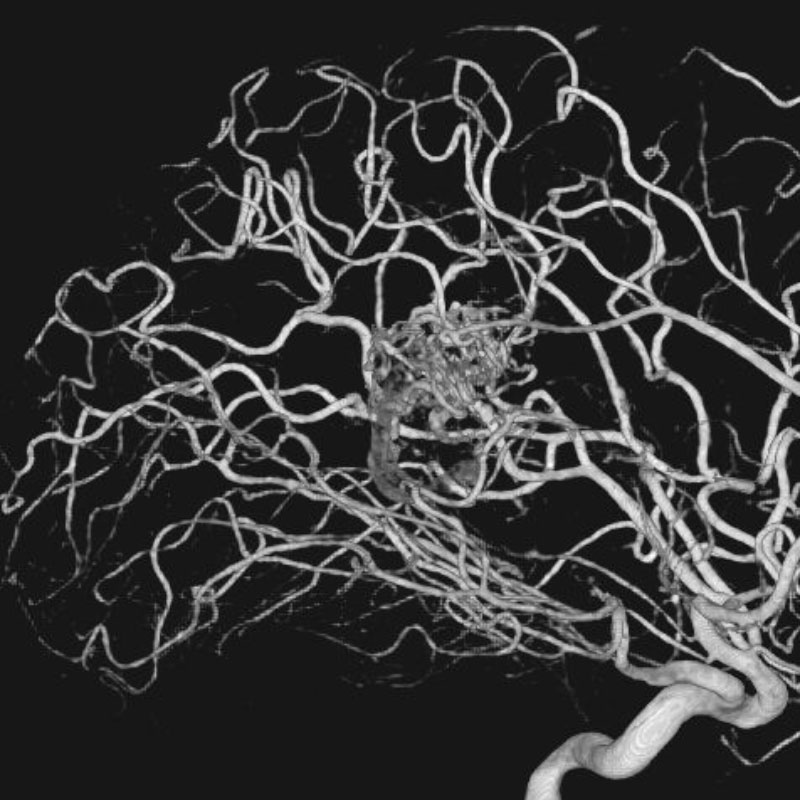

脳動静脈奇形

血管塞栓術

松田/濵田/元永